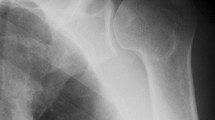

Ultrasonography was performed on both shoulders to diagnose RCT, following the methodology outlined by Middleton et al.18, utilizing a LOGIQ e device (GE Health Care, USA) with linear-array probes set at 12 MHz. To minimize interobserver variability, all ultrasonographic evaluations were conducted by a single experienced shoulder surgeon who was unaware of the other evaluation components. According to Takagishi et al.19, signs of discontinuity and thinning in the rotator cuff were interpreted as evidence of full-thickness rotator cuff tears. Participants were categorized into two groups based on the ultrasonographic findings: those with a rotator cuff tear (the “RCT group”) and those without (the "non-tear group").

The RCT group represented 31.3% (148 out of 472 shoulders) of the participants, while the non-tear group made up 68.7% (324 out of 472 shoulders). The proportion of individuals in the RCT group across different age brackets was 0% for those in their 20s (0 out of 4 shoulders), 14.2% for those in their 30s (4 out of 28 shoulders), 21.7% for individuals in their 40s (10 out of 46 shoulders), 26.2% in their 50s (42 out of 160 shoulders), 23.6% in their 60s (34 out of 144 shoulders), 26.8% in their 70s (22 out of 82 shoulders), and 25% in their 80s (2 out of 8 shoulders), indicating a rise in prevalence with advancing age (Fig. 1).